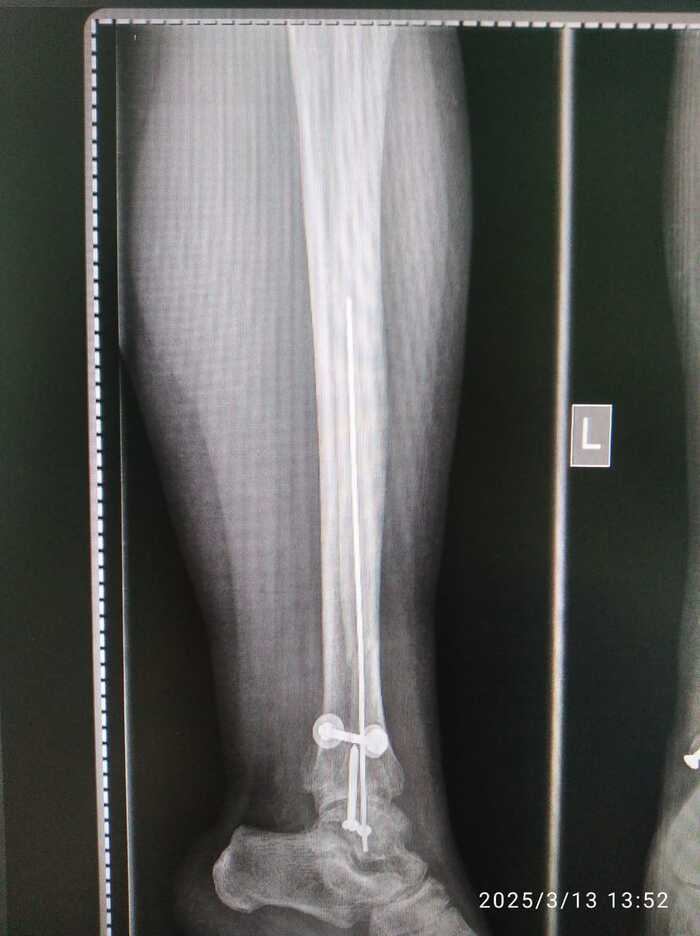

Мама сломала ногу 19 ноября 2024 года. Неудачно упала с дивана - перелом в трёх местах со смещением и разрывом связок. Ниже снимки сразу после операции

Поставили такие спицы. Прощу прощения, я не врач и могу неправильно употреблять некоторые термины.

Ниже прилагаю сегодняшние снимки.